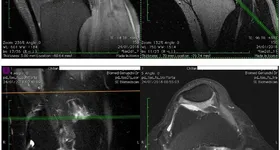

Florin Chilian a trecut ieri prin clipe delicate, după ce timp de 20 de ani a avut dureri chinuitoare de genunchi. Tot coşmarul său a ţinut atât de mult, pentru că mai mulţi medici i-au spus că suferă de artroză, când, în realitate, avea o ruptură de menisc şi tendoane. La câteva ore de la intervenţia dificilă de ieri, talentatul artist a făcut declaraţii şi a împărtăşit o poză cu el pe patul de spital. În imagine se observă că genunchiul stâng este bandajat.

„Este un şir de întâmplări pline de amărăciune. Prea mare şir de diagnostice puse greşite. Peste 20 de ani de dureri destul de rele. Medicii au zis că am artroză, am făcut câteva RMN-uri. Mi-au zis că trebuie să merg la privat, unde costa de cinci ori mai mult. Problema este că , cu acelaşi RMN, am fost la toţi aceşti domni doctori, mi-e foarte greu să spun asta. Sunt nişte bişniţari ordinari care se joacă cu sănătatea oamenilor. Mi-a spus că e rupt şi că dreptul nu e de operat. L-am vulcanizat cu nişte pătrunjel. Mâine, într-o oră-două scap de o problemă pe care o am de aproape de 20 de ani. Stângul, care e mai praf, e mai puţin dureros. De câţiva ani am început să mă reinteresez de asta. E o intervenţie mini-invazivă. Sper să fie ok”, a declarat artistul în cadrul unei emisiuni pe 31 ianuarie.